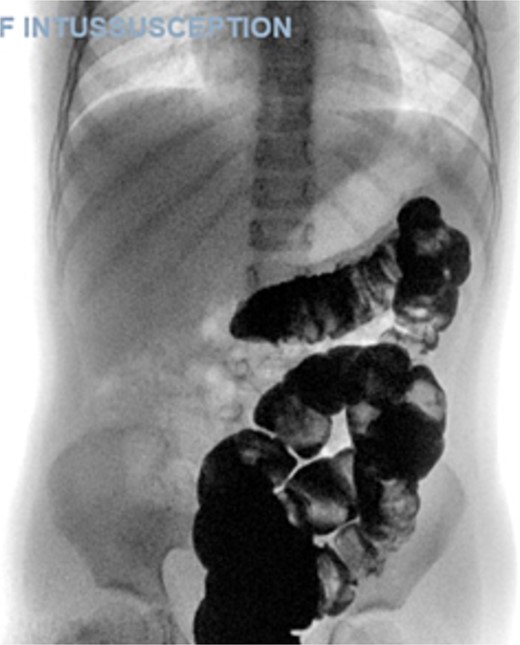

The blood tests showed raised inflammatory markers. An abdominal ultrasound confirmed the presence of intussusception (Fig. 2). A decision was made for a laparoscopic reduction of the intussusception and inspecting for a leading point. A MD was demonstrated and resected accordingly (Fig. 3). The location of intussusception was at the ileo-cecal area. The affected bowel was viable. The position of the MD was in the terminal ileum and it was the lead point for the intussusception. No lymph node involvement. Also, a tumor located at the base of the MD ~4 mm from the resection margin, was found and resected.

Ultrasound of the abdomen showed a target sign of intussusception (5th attack).